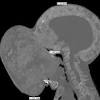

Doctors will remove a tumor the size of a basketball from boy's face An X-ray of the 10-pound, basketball-size tumor on the face of Emanuel Zayas, 14, of Cuba. Doctors at the University of Miami Health System at Jackson Memorial Hospital will perform surgery to remove the tumor on Jan. 12, 2018.

Florida doctors to remove 10-pound facial tumor that threatens to break boy's neck It started out as what his mother thought was just a pimple, a small indignity for a boy beginning puberty. About two years later, what appeared to be a blemish has grown into a 10-pound tumor on 14-year-old Emanuel Zayas' face.